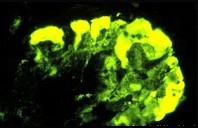

图-1为HE染色,图-2为PAS染色,图-3免疫荧光镜下可见IgM团块状沉积于病灶区,图-4电镜下可见上皮细胞足突广泛融合,系膜增生(M)。阅读这些病理图...

问题 图-1为HE染色,图-2为PAS染色,图-3免疫荧光镜下可见IgM团块状沉积于病灶区,图-4电镜下可见上皮细胞足突广泛融合,系膜增生(M)。阅读这些病理图片,诊断其病理类型是 ( )

选项 A.系膜增生性肾小球肾炎. B.膜增生性肾小球肾炎 C.局灶性节段性肾小球硬化 D.肾小球轻微病变 E.局灶性肾炎

答案 C